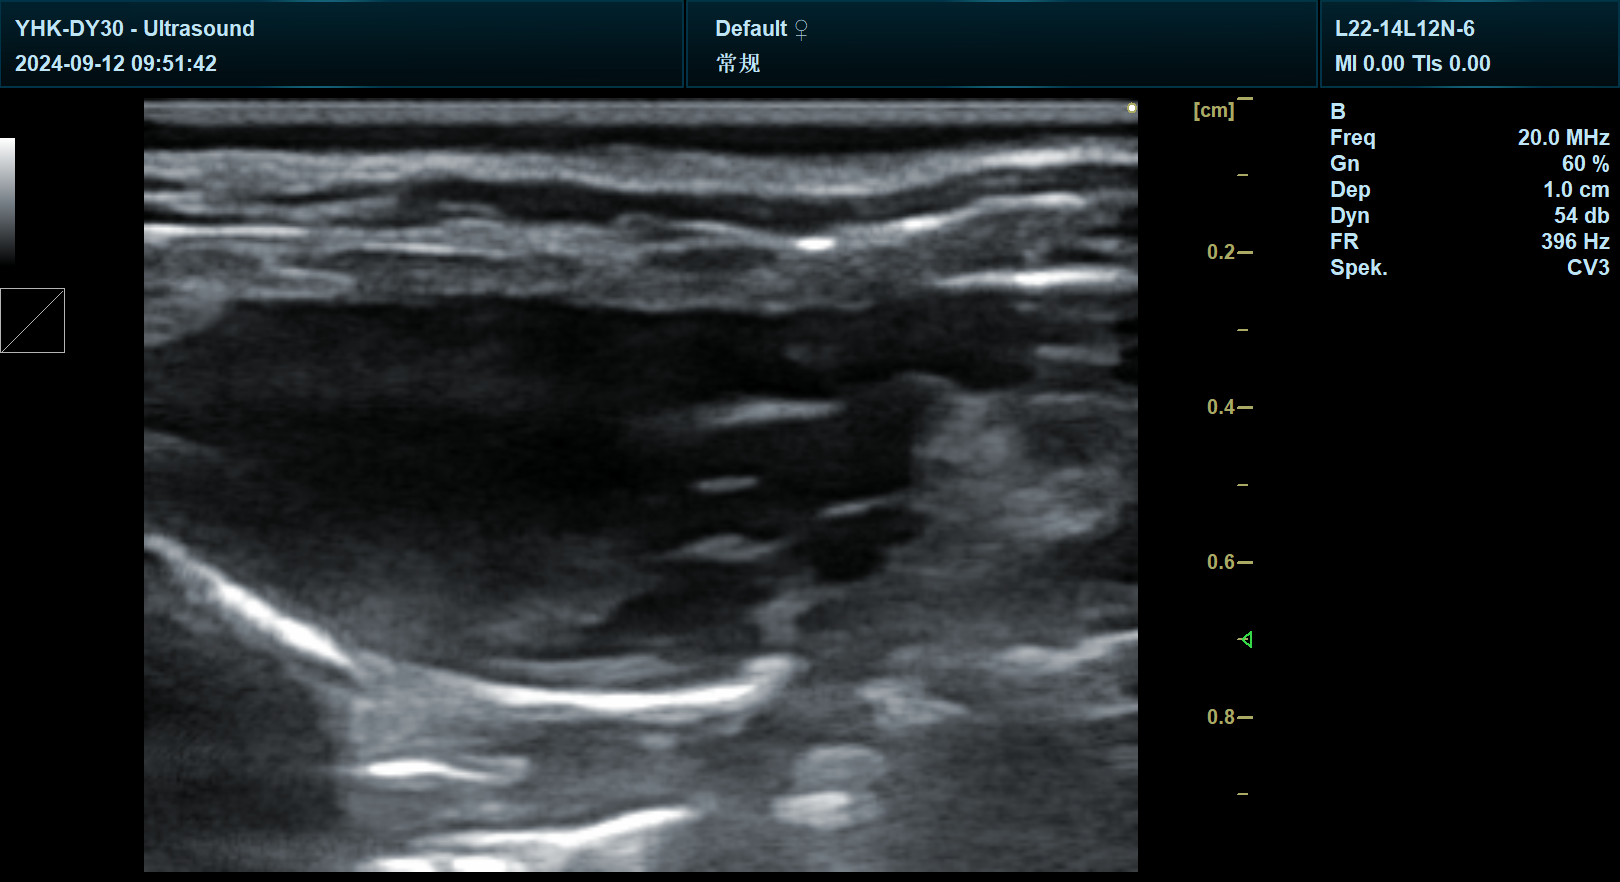

传统科研手段往往依赖离体组织分析或静态成像技术,但生命系统的动态性决定了研究者需要更接近真实生理状态的观察工具。以基因治疗研究为例,科研人员需实时追踪基因载体在体内的分布、评估基因表达效果,并监测潜在的组织炎症反应。若使用普通临床彩超,其成像分辨率与功能模块难以满足科研级需求,而宜慧康专业版彩超通过0.1mm级微米级分辨率与多模态成像技术,可清晰捕捉基因载体在细胞层面的扩散路径,甚至通过血流动力学分析间接量化基因表达强度。

针对科研场景对分辨率的极致需求,宜慧康研发了自适应波束合成技术,通过动态调整超声波发射角度与接收灵敏度,将图像信噪比提升40%。在肿瘤模型研究中,该技术可清晰区分2mm以下的微小病灶与周围正常组织,甚至通过超声造影模式捕捉肿瘤新生血管的动态生成过程,为抗血管生成药物研发提供关键证据。